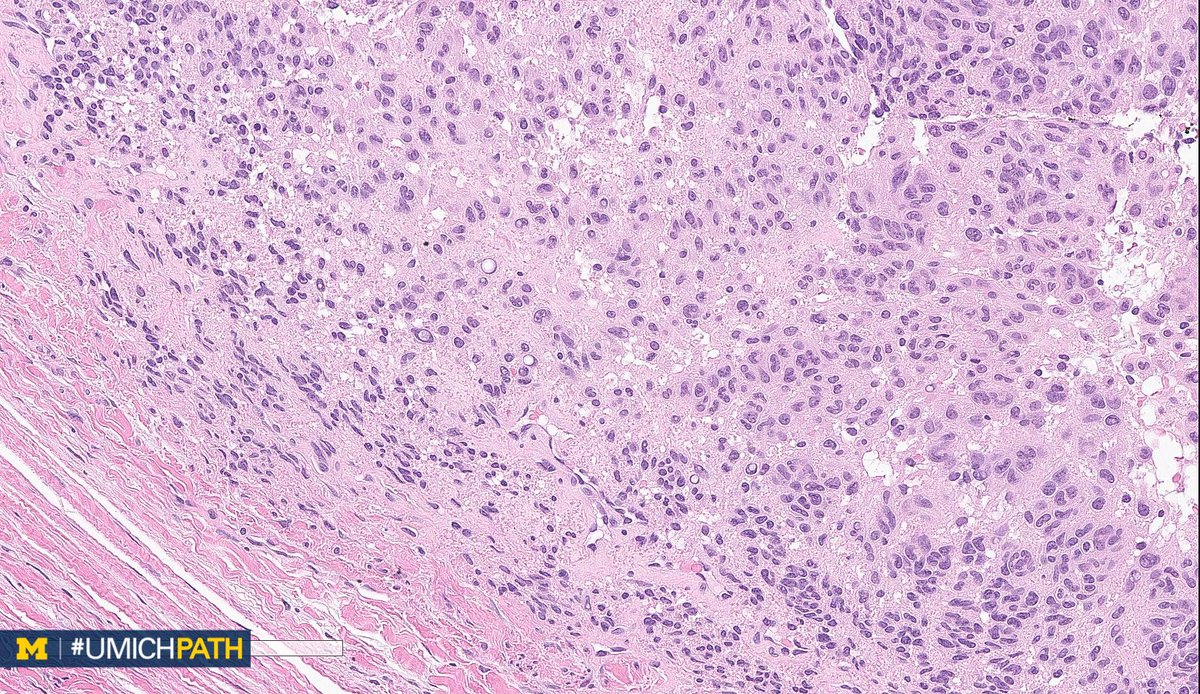

Bone and Soft Tissue #Pathology, day 2

What's your #DifferentialDiagnosis of this superficial soft tissue mass?

What #DailyDx do you favor, and what confirmatory stain(s) would you order?

We’ll tweet the answers and some quick facts tomorrow! #UMichPath#BSTPathpic.twitter.com/BkXUiAuRzg